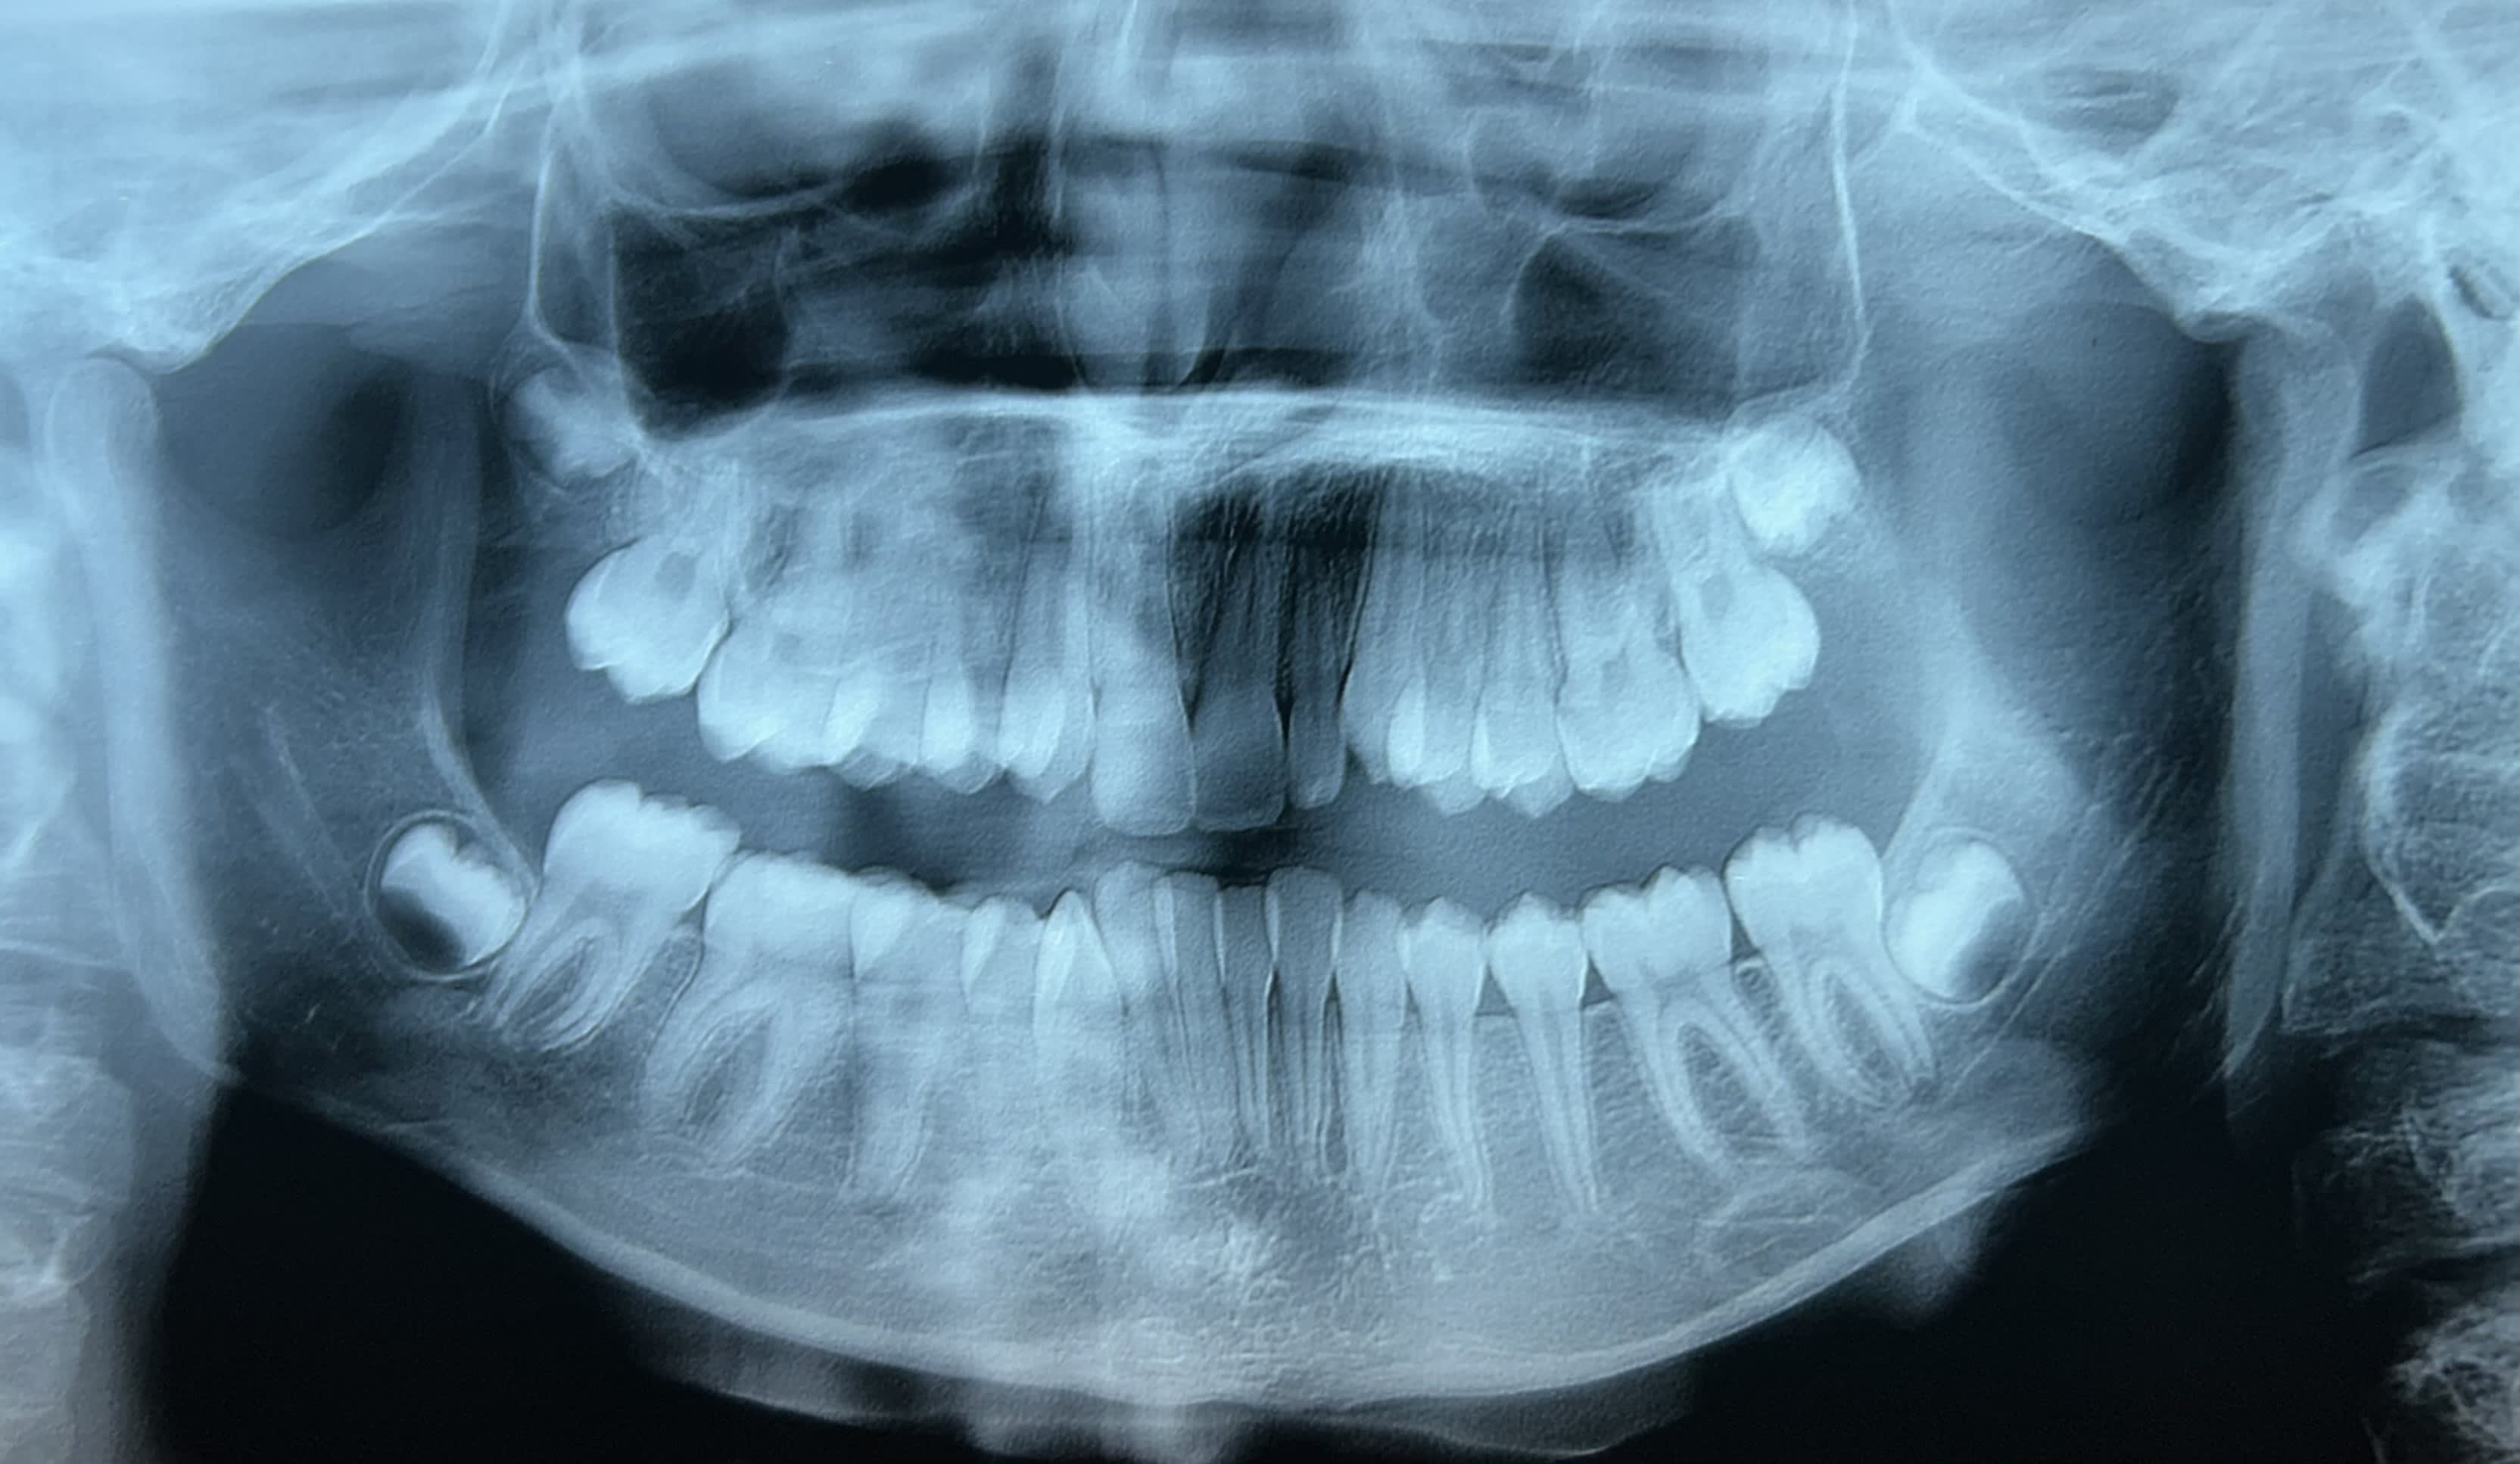

Jeune fille de 11 ans et demi, hypodivergente tendance classe III squelettique (mais classe II dentaire) et biretroalveolie. Agénésie de 12 avec évolution de 13 à sa place et 22 rhyziforme.

Personnellement, bien qu’il y ait un fort encombrement mandibulaire j’aurais aimé éviter si possible les extractions au vu du profil.

Pour ouverture espace et remplacement 12 je pensais à :

- un motion carrière classe II pour commencer à corriger la classe II et ouvrir l’espace de 12. Puis poursuivre avec le multi attache Genius.

- extraction des 4PM1 et alignement. Mais délétère pour le profil … ⚠️

Si les parents refusent l’option d’ouverture d’espace :

- 13/23 en place de 12/22 et extraction 22 + PM1 mandibulaire… ⚠️ profil …

- alignement sans extractions avec système Genius et laisser 13 en place de 12 et 22/23 à leur place. + éventuelle coronoplastie par composite en fin de traitement ?

Je n'extrairais sous aucun pretexe 14.24 dans cette situation. La classe dentaire sur un profil comme ça est le cadet des soucis je pense. Face first !

Ouvrir l'espace en secteur 1 tu vas galerer .. meme avec un carriere

Le repositionnement incisif bas est marqué non ? Je me tate à te dire d'envisager une incisive mandibulaire . Le milieu est comment ?

Le profil très rétrusif, la typologie verticale, et la supraclusion sont des éléments en faveur de l’ouverture d’espace afin de contrôler au mieux la position de l’incisive maxillaire.

Dans ces cas relativement fréquents d’agénésie d’incisives latérales, on a plutôt tendance aujourd’hui à traiter par fermeture d’espace pour éviter au maximum les prothèses et les implants antérieurs, sources potentielles de problèmes futurs. Vous êtes capable, vous, de garantir un bridge cantilever ou un implant 80 ans (voir l’espérance de vie…) ?

Ici, le plan de traitement de fermeture d’espace me paraît d’autant plus évident qu’on est déjà en classe II molaires :

Avulsion 22 et mésalisations supérieures (on parfait la classe II molaires des 2 côtés).

Moyens : TIM (on peut allègrement prendre appui sur l’arcade inférieure puisqu’on doit même faire de la place pour les incisives). Si c’est insuffisant, VIS au niveau antérieur, de chaque côté de l'orifice piriforme.

On finit en classe II canines thérapeutiques avec des coronoplasties de 13 et de 23.

Avantage : Meilleure stabilité et pas d’implant qui peut poser problème à la fois à sa mise en place (tu as bien vu, Elgy) et au niveau de sa pérennité esthétique (tu as bien vu, sexmo). Je rajouterai que même à 30 ans c’est encore trop tôt (Jean-Marc Dersot).

Si les coronoplasties sont bien faites, ça passe très bien.